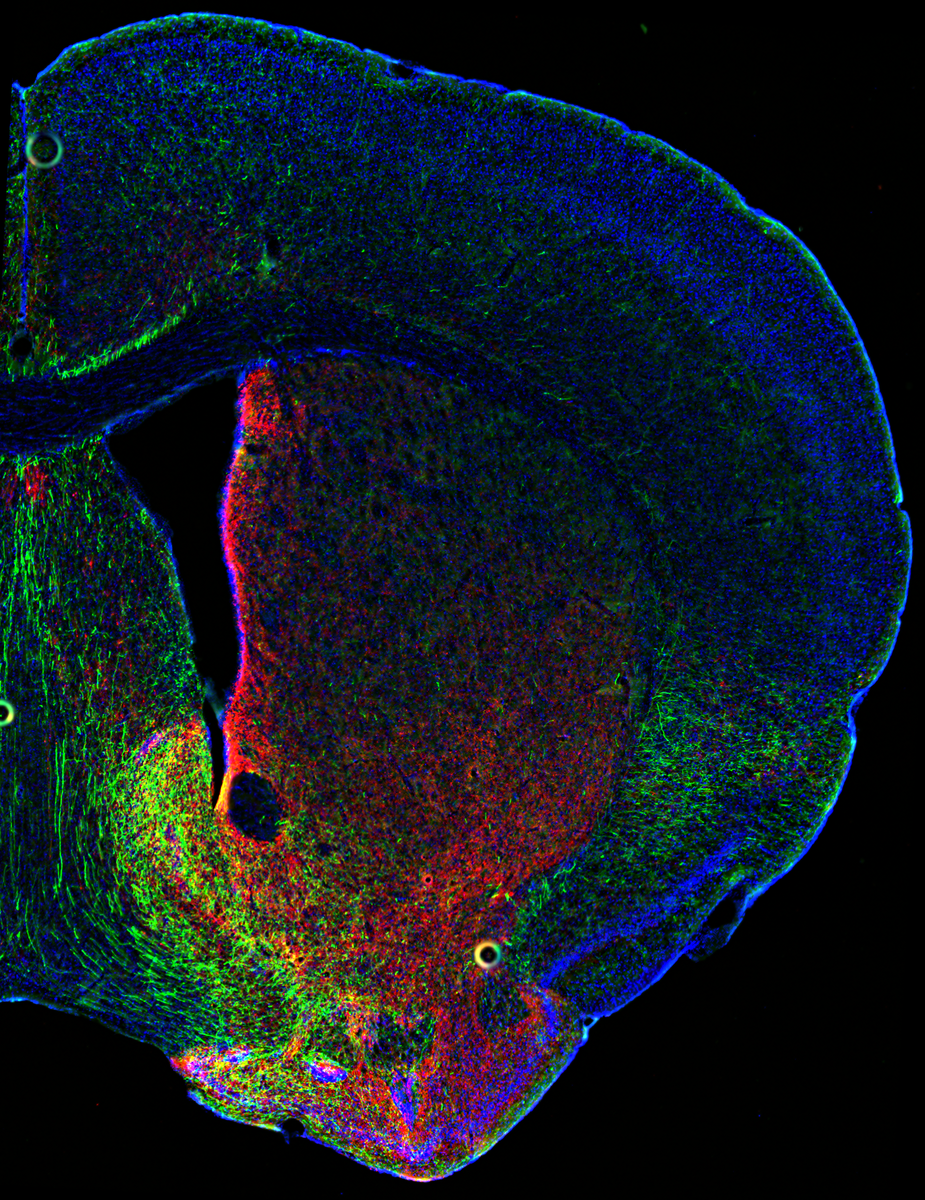

Коронарный срез мозга показывает перекрытие нервных волокон, содержащих дофамин и серотонин, в прилежащем ядре. С разрешения Дэниела Кардозо Пинто, лаборатория Маленка, Стэнфордский университет.